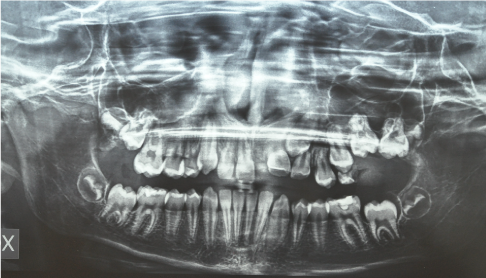

Case 1. A 10 years old male patient presented with a 1 month history of mandibular swelling on the right, asymptomatic. Performed Ortopanthomography and mandibular TCCB an osteolytic lesion is observed that extends from 8.5 to 8.2 with dislocation and retention of 43, 44 and 45 (Figure 1).

Figure 1 Case 1. Initial Ortopantomography